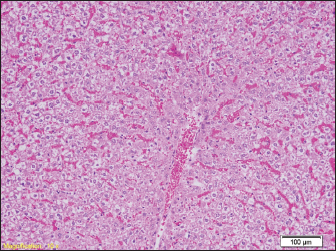

In the liver samples of all groups of rats, relatively uniform changes are observed, which in each sample include a certain degree of congestion, with overcrowding of the centrolobular veins, but also the veins of the portal spaces, as well as the dilation of the sinusoids filled with erythrocytes, while the hepatocytes in places show signs of fluffy degeneration (Figs. 5 and 6.)

Fig. 5. Blood filling of hepatic sinusoids and centrolobular vein (HE, ×100).

Signs of degenerative changes caused by drowning were found in the liver samples. It is believed that drowning and hypotension during recovery lead to irreversible changes in the organs caused by a lack of oxygen. Similar changes were found in other studies, where the liver showed small but numerous clusters of hyaline bodies in the liver sinusoids (Ikeda et al., 1998).

Our results show signs of overcrowding of hepatic sinusoids with partially ballooned hepatocytes. These results were found in previous studies, where hepatocytes had hydropic degeneration (Ibrahim et al., 2022). The changes that can occur to the organs can largely depend on the type of water in which the drowning occurred, from salt water to fresh water. In our study, rats were drowned in water from the Bosnia River. Upon examination of the heart muscle, we found congested blood vessels, with no signs of degeneration. In contrast to our results, Mahrous et al., found signs of cardiac muscle cell damage after drowning in salt water, which were presented as a greater number of vacuoles in the cytoplasm, a reduced number of nuclei in the cells, and an inflammatory infiltrate, but also edema and congestion of blood vessels as in our results (Ibrahim et al., 2022). Christe et al. (2008) found an enlarged heart on the post-autopsy material, with an increased volume of the right atrium and right ventricle, while the left side of the heart was enlarged in only one person (Christe et al., 2008).

However, studies have shown that there are statistical differences in the number of diatoms in false positive cases and actual drowning cases. Therefore, a comprehensive analysis of multiple organs, rather than just one organ, would be more useful for the diagnosis of drowning. Relatively uniform changes are observed in the liver samples of all groups of rats, which in each sample include a certain degree of congestion, with overcrowding of the centrolobular veins, but also the veins of the portal space, as well as dilation of sinusoids-filled with erythrocytes, while hepatocytes in places show signs of paper degeneration.